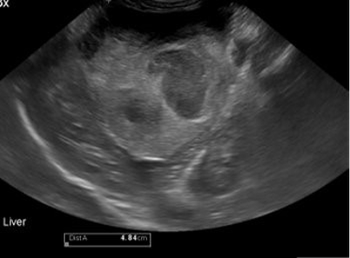

Unlocking insights into diagnosis, treatment, and prognosis in small animal cardiology